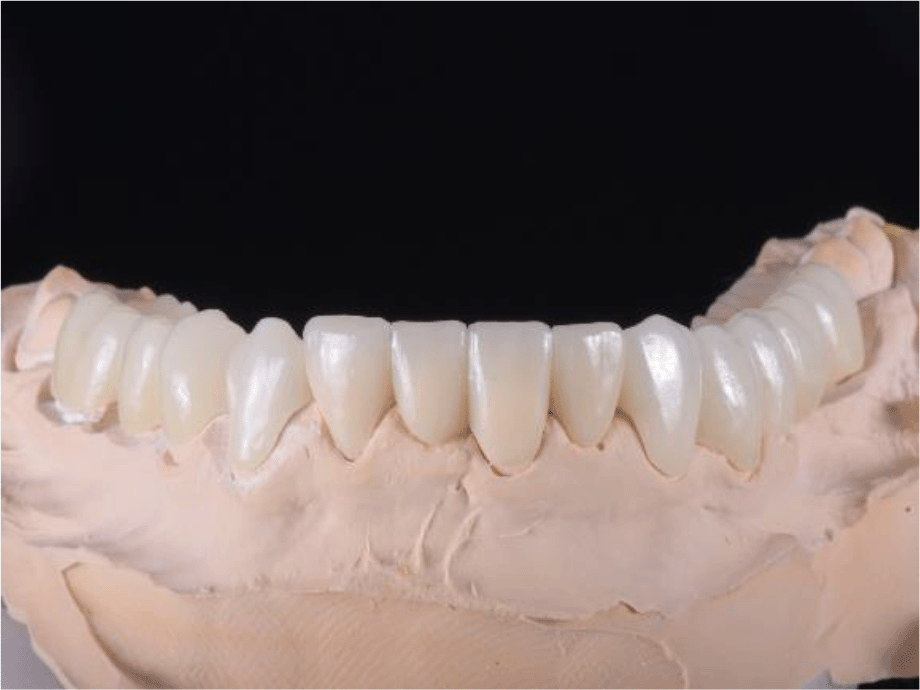

For the adaptation period, it was preferred that the temporary construction of the upper jaw be made of PMMA (Ceramill TempML), which was cemented with temporary cement (Prevision (Kulzer)). This construction was intended to remain in the patient’s mouth throughout the period of adaptation and, if necessary, to be optimized (Figures 11 and 12).

26dd931c-41d3-478d-bec1-8cb211d0a4b8_figure11.gif

Figure 11. PMMA crowns on a model.

26dd931c-41d3-478d-bec1-8cb211d0a4b8_figure12.gif

Figure 12. PMMA crowns cemented in the mount.